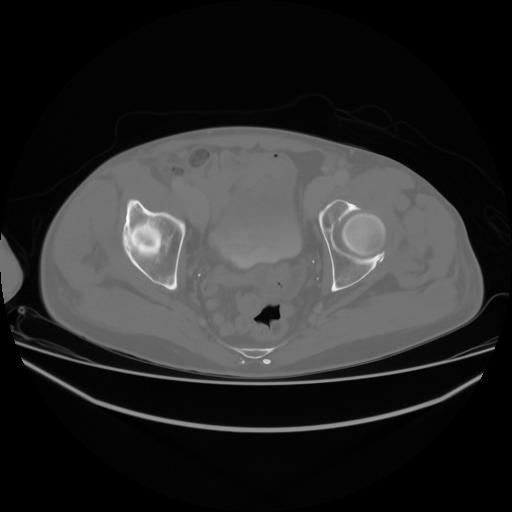

4 CUERPO,CE,Axial,3.0,CUERPO,,